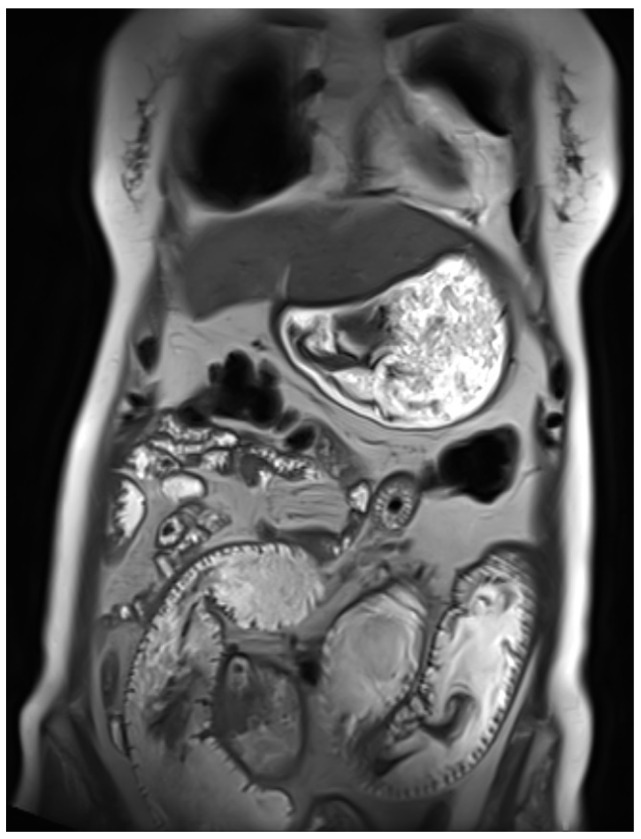

背景:胃肠道神经外胚层肿瘤(GNET),也称为胃肠道透明细胞肉瘤(CCS),是一种罕见的神经嵴源性恶性肿瘤,其特征为EWSR1-ATF1或EWSR1-CREB1融合。由于其罕见性,证据有限,没有标准管理的既定指南。GNET具有侵袭性,局部复发、转移和死亡率高。病例介绍:我们报告了一名46岁的女性,她有胃肠道癌症家族史,于2020年被诊断出患有肠道GNET。她接受了段性肠切除术作为多模式治疗的第一步。经过三年的随访,她出现了肝脏和腹膜转移。2023年11月,她开始联合使用抗vegf酪氨酸激酶抑制剂cabozantinib和免疫检查点抑制剂nivolumab。患者病情稳定18个月,耐受性良好,无不良事件发生。肿瘤的分子分析显示EWSR1-CREB1融合,支持选择靶向治疗和免疫治疗作为首选治疗方法。结论:免疫治疗和靶向治疗显示出GNET/CCS治疗的前景,但缺乏临床标准,证据主要来自病例报告。需要更多的数据来确定这种非常罕见疾病的最佳治疗顺序和组合。

Background: Gastrointestinal neuroectodermal tumour (GNET), also known as clear cell sarcoma (CCS) of the gastrointestinal tract, is a rare neural crest-derived malignancy characterized by EWSR1-ATF1 or EWSR1-CREB1 fusions. Due to its rarity, there is limited evidence and no established guidelines for standard management. GNET is aggressive, with high rates of local recurrence, metastasis, and mortality. Case Presentation: We report the case of a 46-year-old woman with a family history of gastrointestinal cancers who was diagnosed in 2020 with an intestinal GNET. She underwent a segmental enterectomy as the first step of multimodal therapy. After three years of follow-up, she developed hepatic and peritoneal metastases. In November 2023, she began combined therapy with the anti-VEGF tyrosine kinase inhibitor cabozantinib and the immune checkpoint inhibitor nivolumab. The patient has maintained stable disease for 18 months with good tolerance and no adverse events. Molecular analysis of the tumour, which showed an EWSR1-CREB1 fusion, supported the selection of targeted therapy and immunotherapy as the preferred treatment approach. Conclusions: Immunotherapy and targeted therapy show promise for GNET/CCS treatment, but clinical standards are lacking, and evidence comes primarily from case reports. Additional data are needed to determine the best sequence and combination of therapies for this very rare disease.